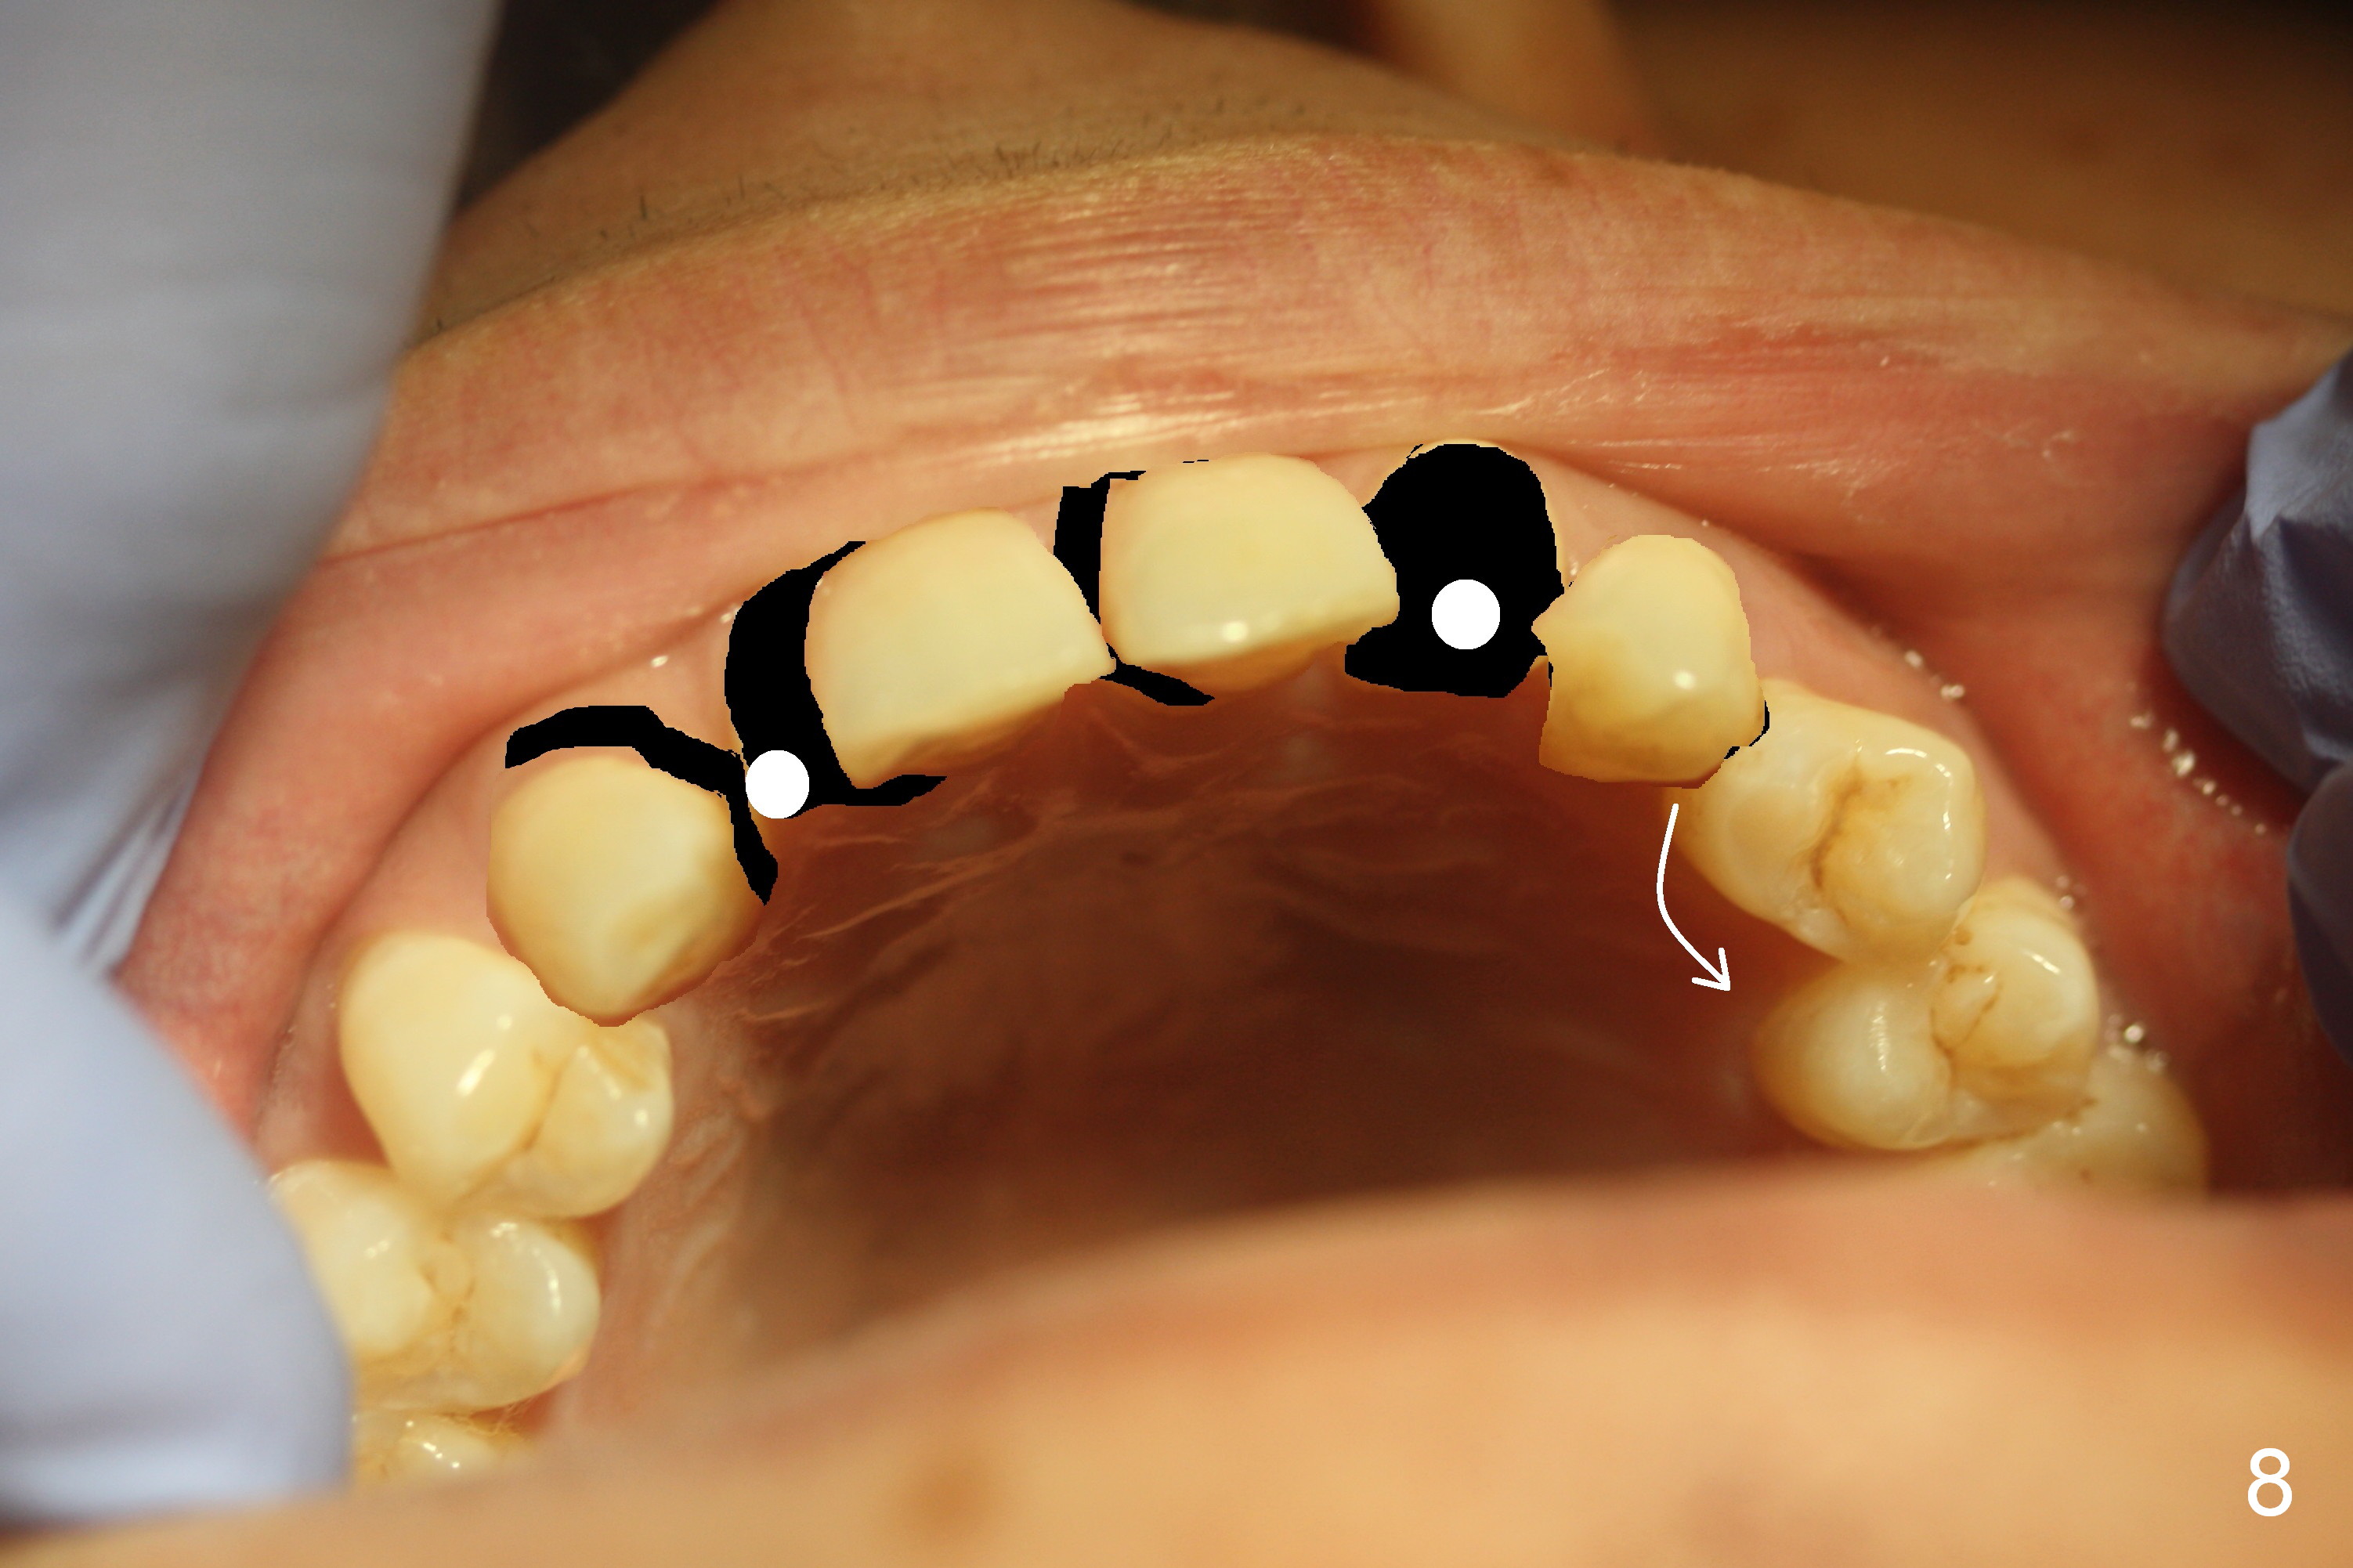

A 38-year-old man has congenitally missing laterals (Fig.1,2) with retention of a deciduous canine (Fig.2,3 C). UL 4 (upper left 1st bicuspid) rotates (Fig.3). LR7 has been extracted (Fig.4).

To improve cosmetics, extract the deciduous tooth (Fig.5), place brackets for the maxillary teeth (6-6), including a lingual button on UL4 to correct the rotation and distalize U3s (Fig.6), close the upper midline diastema and change the midline if needed (Fig.7) and finally place small-diameter implants at U2s (Fig.8 white circles).